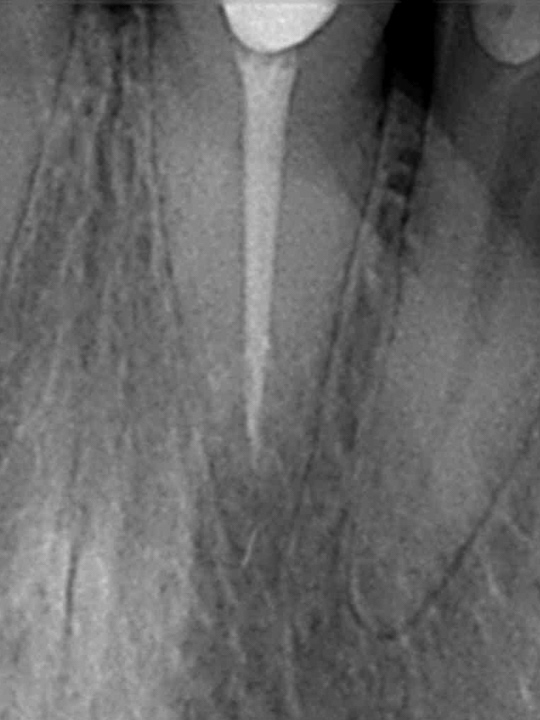

PRZYKŁAD 4